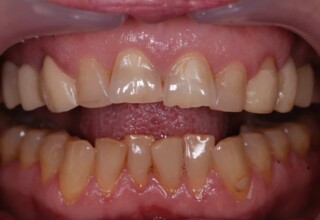

Composite Resin Veneers

Resin veneers are an inexpensive mode of esthetic improvement of anterior teeth, premolars also. Their potential is admirable and their limit is the operator’s clinical dexterity and imagination. In this case there were multiple problems with the upper four incisors: staining, poor inclinations, diastemas, multishading, poor interrelationship and poor tooth-gingiva ratios. They were restored with four direct composite resin veneers (one on a porcelain implant crown!) which were manufactured intraorally!!!